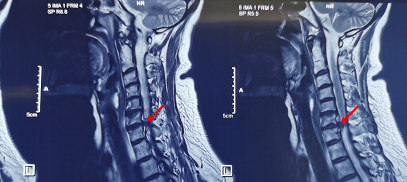

术前矢状位MRI,红色箭指向椎间盘严重突出,压迫髓腔

术前轴位MRI,红色箭指向椎间盘严重突出,压迫髓腔

术后矢状位和轴位MRI,红色箭指示压迫髓腔的椎间盘成功摘除